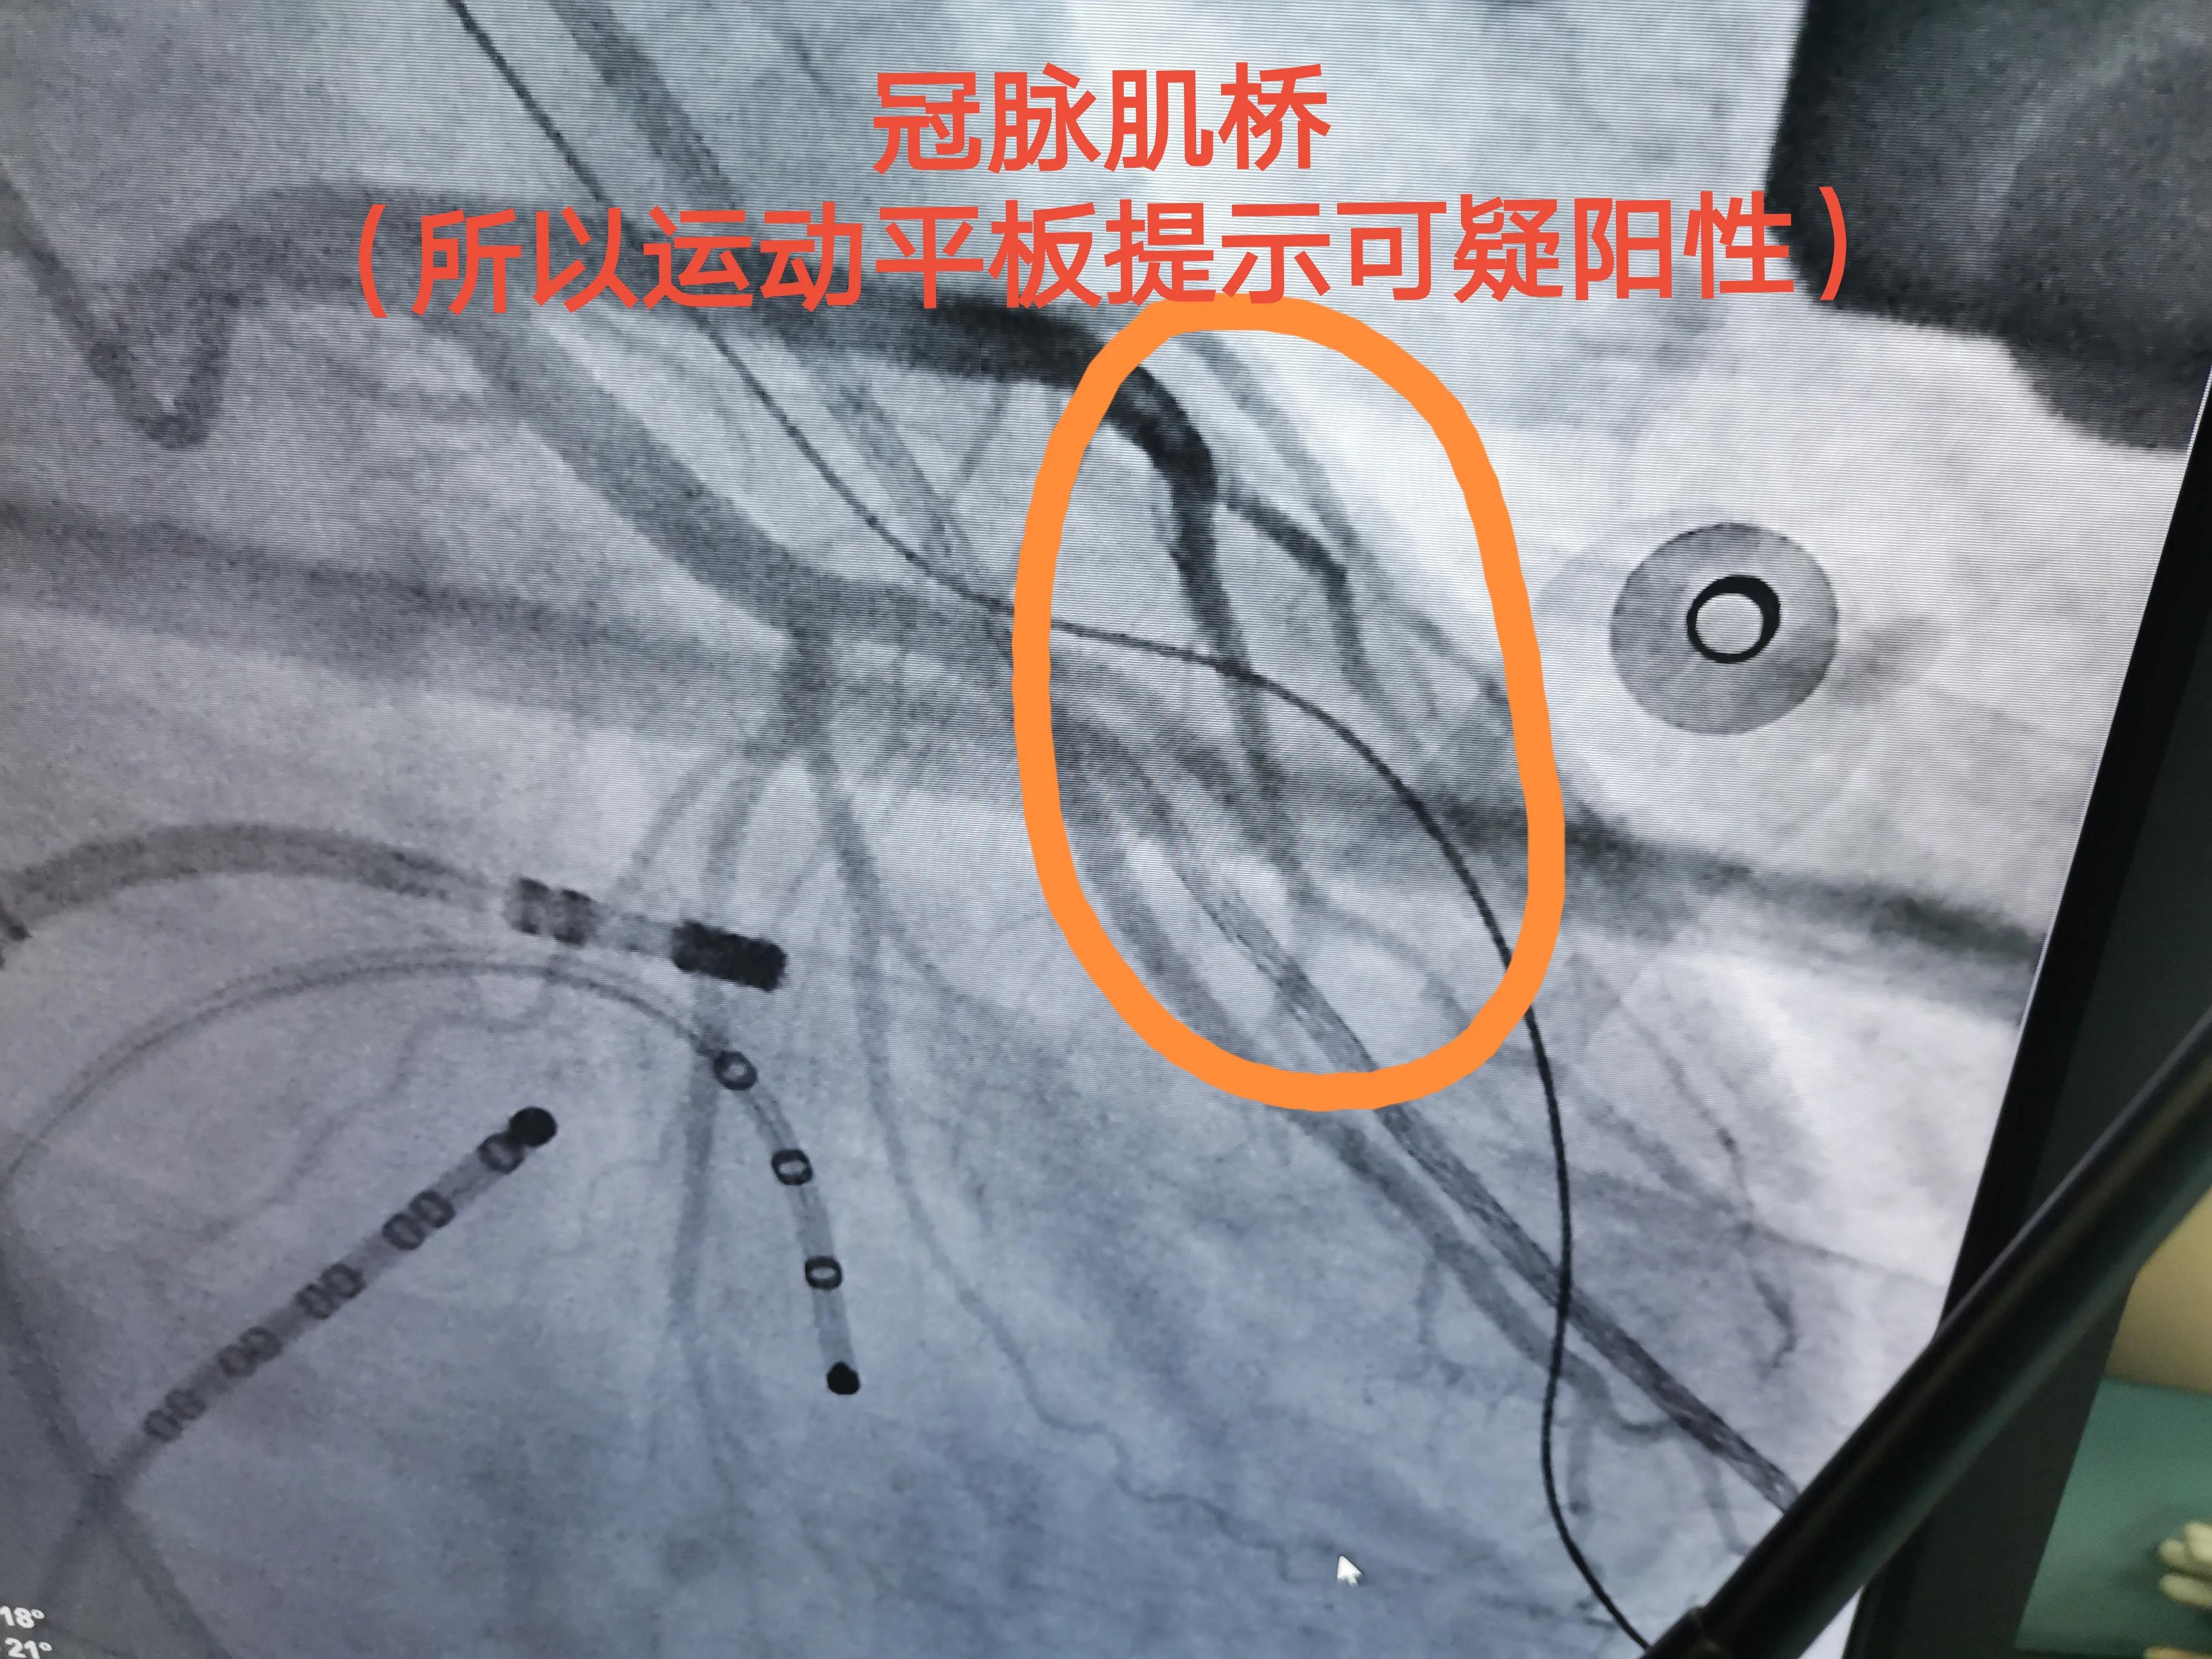

常规血和胸片、holter、心超无殊,做了个运动平板,是个“可疑阳性”

可疑阳性,提示心脏冠脉狭窄可能性大(如果是阳性,可能性更大)

视察期间做了造影,病人没有什么冠心病危险因素,运动平板阳性,果然是“冠脉肌桥”引起的,放心了!